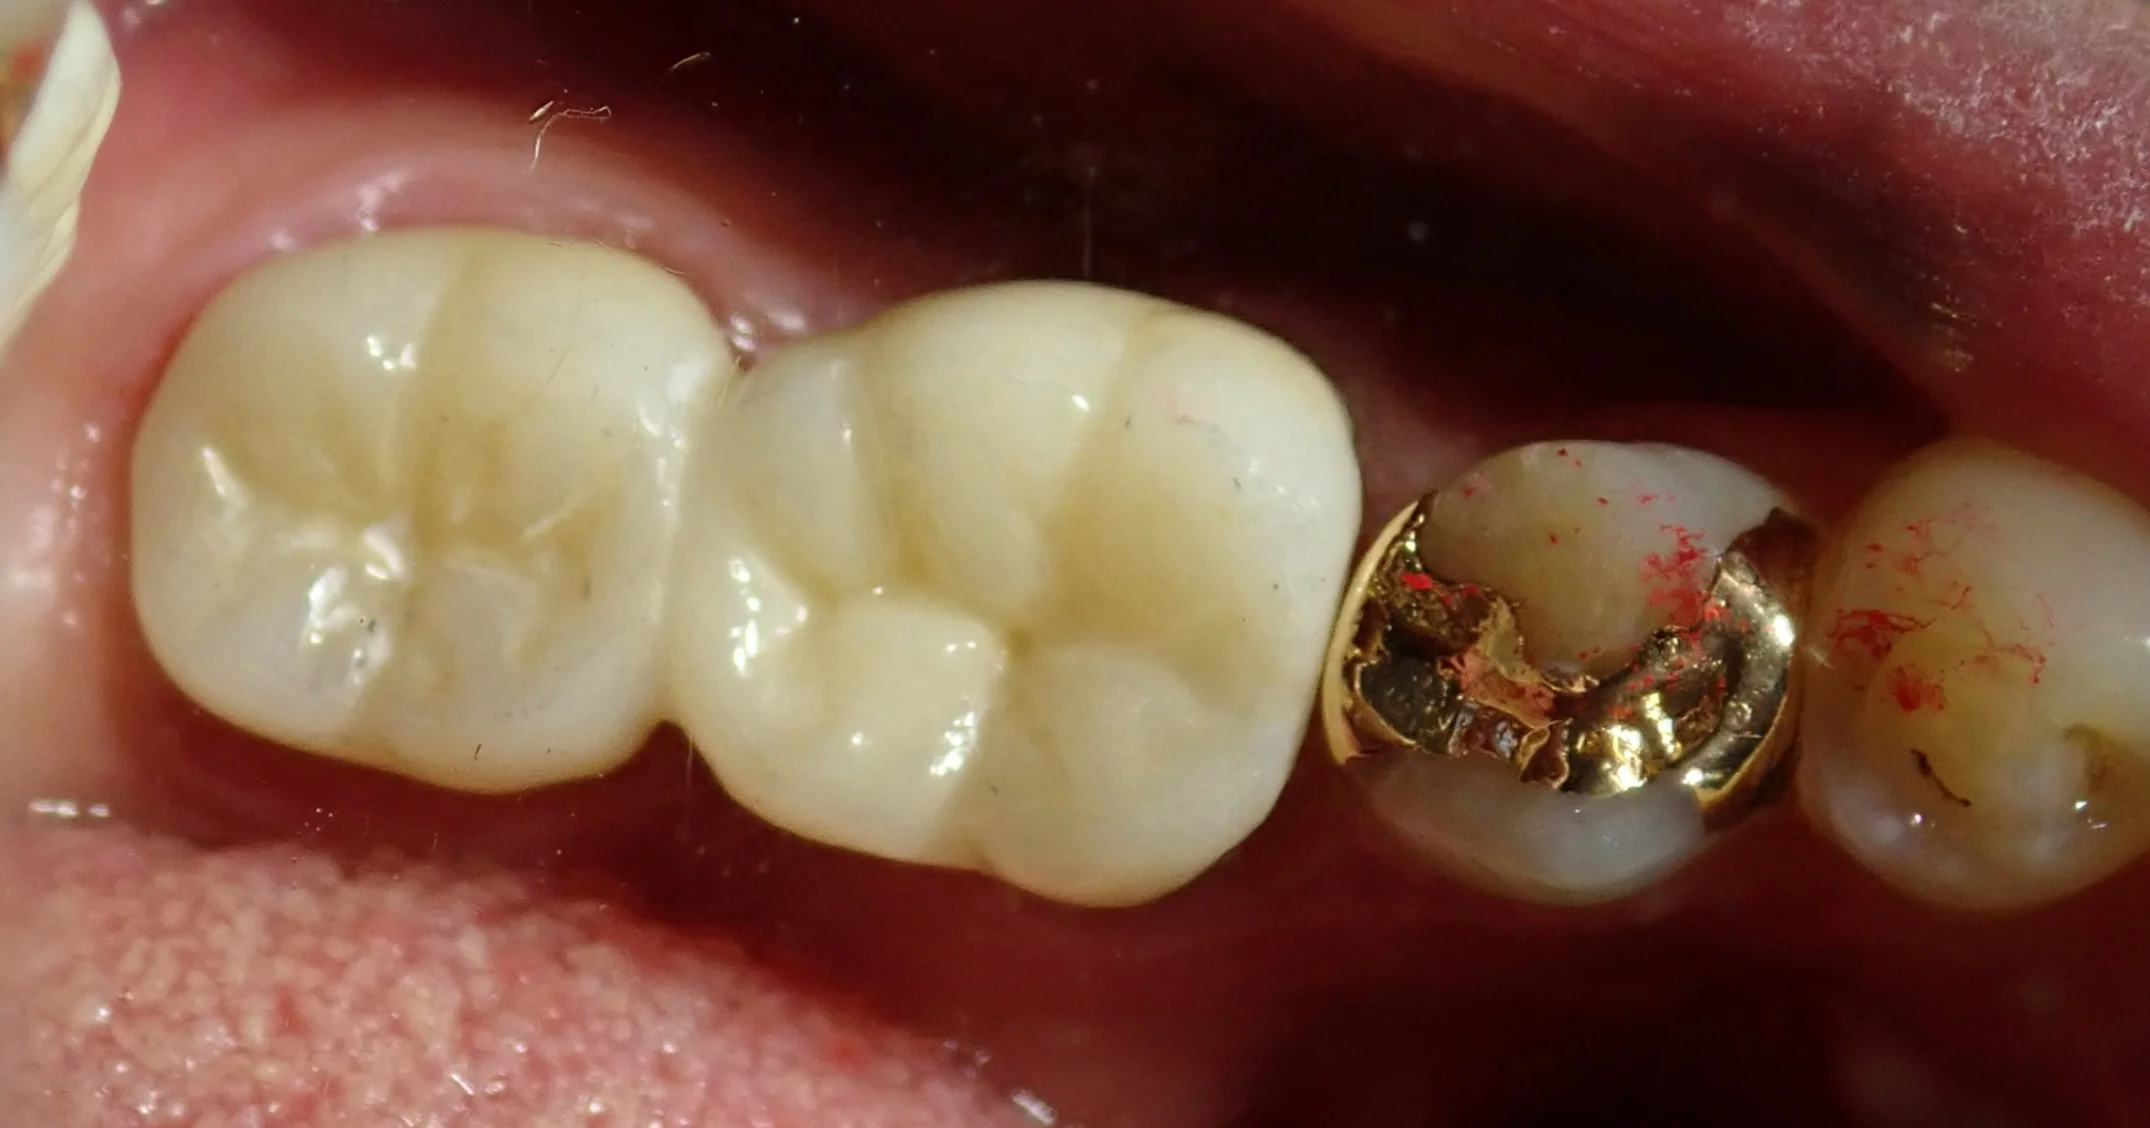

で、セラミックを装着した模型がこちらです。

見た感じ普通に2本の歯っぽく見えるように仕上げてもらいました。

歯がない所謂「ダミー部」については歯間ブラシやブリッジ用のフロスを通せるように若干の隙間を作っています。

実際のお口の中の写真がこちらです。

着けた後がこちらですね。

適合良く大きな調整なく綺麗に入ってくれました。

普通歯根破折で抜歯を行う際には、問題の無い根まで抜いてしまう事が結構ありますが、それをするとブリッジを作る際に一つ手前の歯まで大きく削る羽目になってしまいます。

2本の根がどちらもダメになっているのであれば仕方ありませんが・・・

残せるのであれば残してあげたほうが、10年20年後に見た時に圧倒的に有利かと思います。

今回の方は保険診療でのやり直しに嫌気がさしたとのことで自費診療のセラミックで行いましたが、この治療方法は保険適用内ですので、普通に保険の金属のもので仕上げることも出来ます。

歯科医師から「抜くしかない」と言われても、1本でも根が残ることで治療の選択肢が広がりますし、健康面でも経済面でも有利ですので、『どちらかを残すことが出来ないか』を抜く前に聞いておくのがお勧めです。